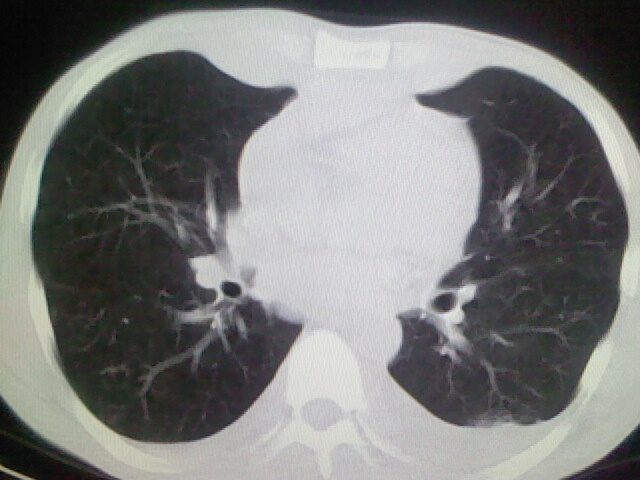

以下是引用杀毒软件在2008-9-3 6:11:00的发言:[br]侵袭性胸腺瘤------一般不侵到气管旁[br][br]考虑----纵隔淋巴瘤,心包及胸膜受累

以下是引用随光逐影在2008-9-3 7:07:00的发言:[br]1)考虑淋巴瘤可能。2)双侧胸腔积液(以左侧为甚)。3)心包积液。